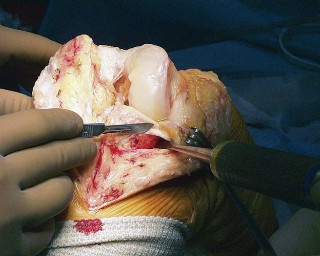

هذه الجراحة ليست مجرد استبدال للمفصل التالف، بل هي عملية تصحيحية شاملة تهدف إلى إعادة المحاذاة الطبيعية للركبة والتخلص من الانحراف التقوسي الذي يسبب الألم ويُسرّع من تدهور المفصل. بفضل الخبرة الواسعة للأستاذ الدكتور محمد هطيف التي تمتد لأكثر من عقدين من الزمن كأستاذ جامعي وجراح عظام متخصص، وباستخدامه لأحدث التقنيات الجراحية مثل الجراحة المجهرية وتنظير المفصل بتقنية 4K وزراعة المفاصل المتقدمة، يتمكن مرضى خشونة الركبة التقوسية في صنعاء من استعادة حركتهم الطبيعية والعيش بلا ألم.

يُعد الانحراف التقوسي مشكلة شائعة وقد يكون خلقيًا (موجودًا منذ الولادة)، ولكنه غالبًا ما يتطور بمرور الوقت نتيجة لخشونة الركبة المتقدمة، حيث يؤدي التآكل غير المتساوي للغضروف إلى تفاقم التشوه. تصحيح هذا الانحراف هو جوهر جراحة استبدال مفصل الركبة التقوسي، وهو ما يتقنه الأستاذ الدكتور محمد هطيف لضمان استقرار المفصل وطول عمره.

تشخيص خشونة الركبة التقوسية

التشخيص الدقيق لخشونة الركبة التقوسية أمر بالغ الأهمية لتحديد أفضل مسار علاجي. يعتمد الأستاذ الدكتور محمد هطيف على نهج شامل يجمع بين الفحص السريري الدقيق والتقنيات التصويرية المتقدمة لتقييم حالة المفصل وتحديد مدى الانحراف التقوسي وتلف الغضروف.